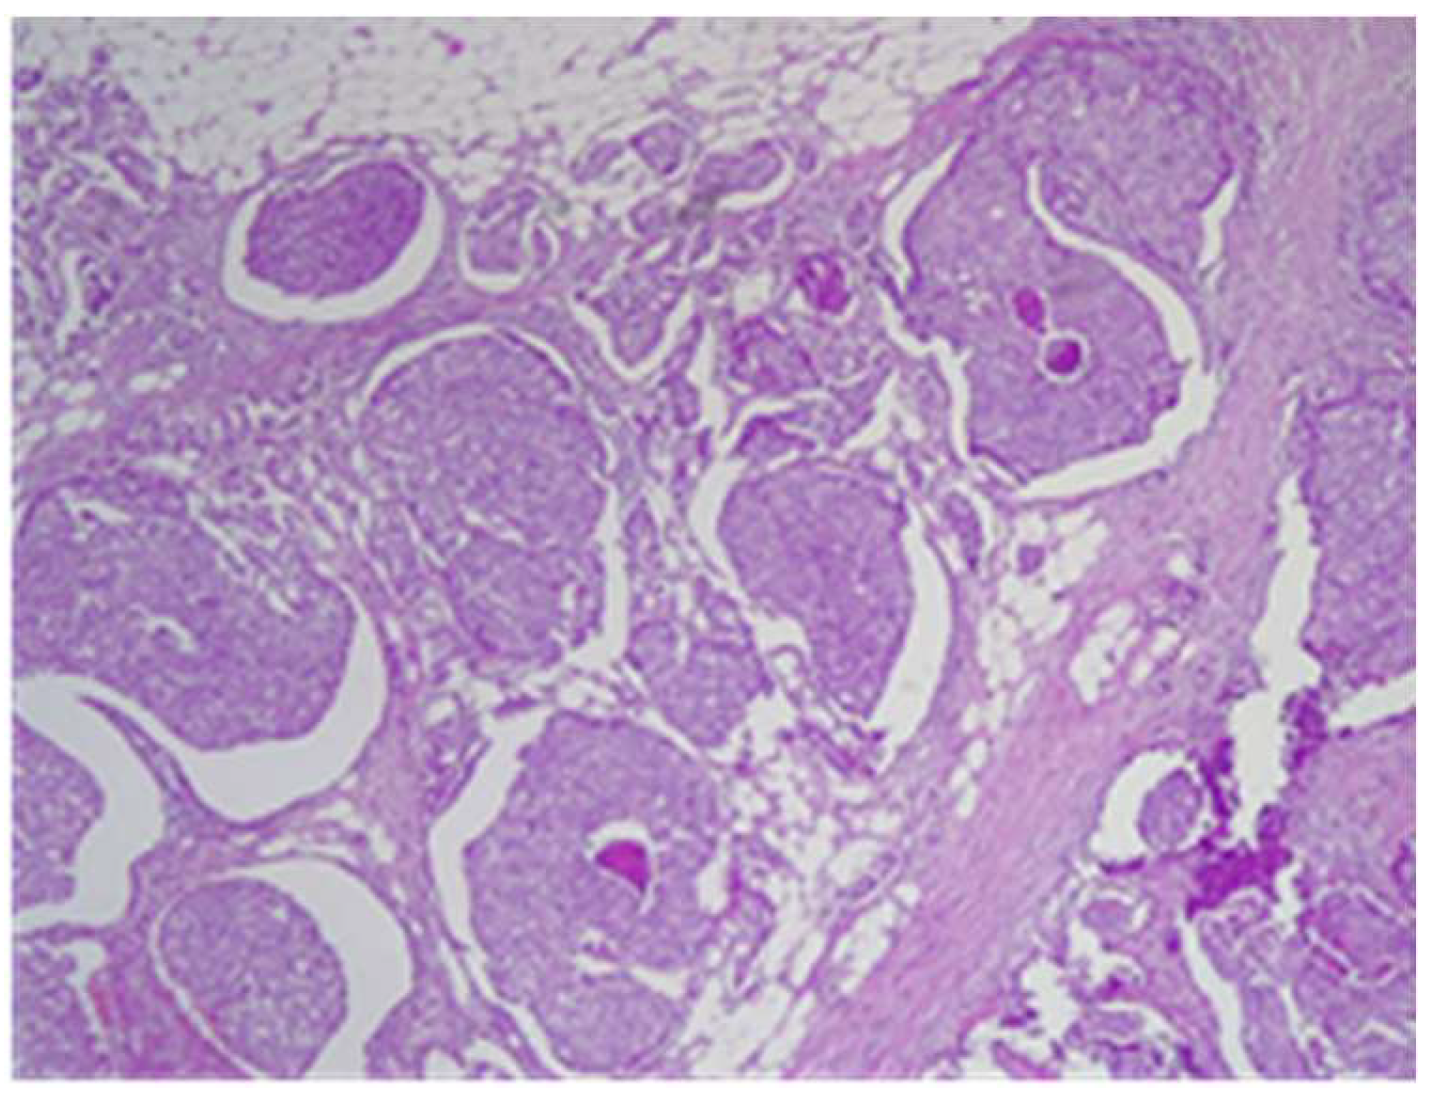

2. Case Report

| Markers | Tumor A—Ductal Invasive Carcinoma | Tumor B—Lobular Invasive Carcinoma |

|---|---|---|

| ER | 90% positive | 90% positive |

| PR | 30% positive | 90% positive |

| HER2 | 2+ | Negative |

| Ki67 | 40% | 10–15% |